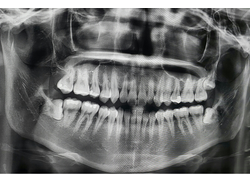

사랑니 발치 후 음식 음주 실밥 제거는 언제? 언제하는지 알아봐요 사랑니 발치 후 음식 음주 실밥 제거는 언제쯤 하는지 등 사랑니 발치 후에 대한 정보를 정리해드리도록 하겠습니다.사랑니는 일반적으로 18-25세 사이에 발생하는 어린 시절 치아 중 3번째 대구치를 말합니다. 대개 상아질로 된 이빨과 마찬가지로 식이기구의 역할을 합니다. 하지만 대개 다른 이빨보다 공간이 좁아 자리를 잡지 못하고 다른 이빨과 충돌할 가능성이 높습니다. 이로 인해 충돌로 인한 주변 치아의 이상을 유발할 수 있고, 때로는 발치가 필요합니다. 또한, 사랑니 발치 시 치아 근육통, 치은염, 치아 골수염 등의 문제도 발생할 수 있습니다. 따라서, 꾸준한 치과 검진과 개인적인 구강 관리가 중요합니다.

사랑니 발치는 부분 마취를 진행 후 수술실에서 이루어집니다. 수술 전에는 환자의 건강 상태와 치아의 위치와 상태를 파악하기 위해 치과 전문의가 진단을 수행합니다.

수술 중에는 치과 전문의가 주변 치아와 잇몸을 보호하기 위해 블록 등 잇몸을 보호하기 위한 장치를 사용 사랑니를 뽑게 됩니다.